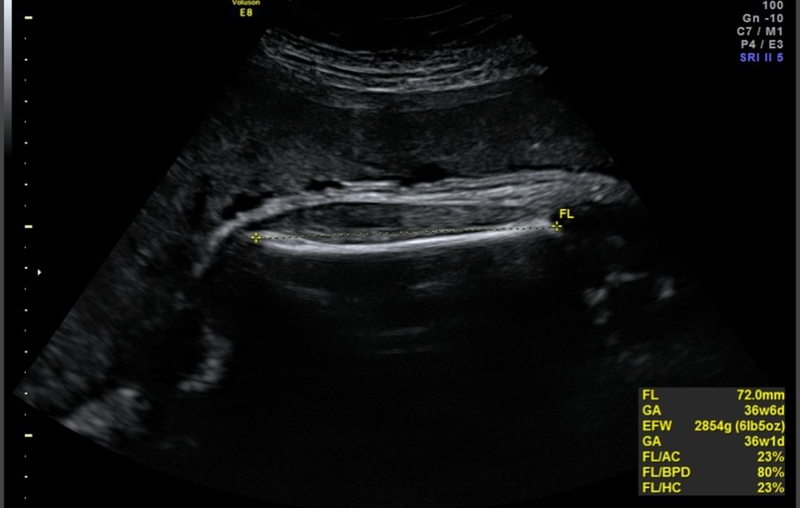

Chỉ số chiều dài xương đùi hay chỉ số FL trong siêu âm thai là một chỉ số quan trọng cần theo dõi trong quá trình phát triển của thai nhi. Đây là chỉ số đo lường chiều dài từ đầu trên đến đầu dưới của xương đùi - xương dài nhất trong cơ thể. Thông thường, việc đo chiều dài xương đùi được thực hiện qua siêu âm thai. Hình ảnh siêu âm sẽ cho biết thông tin chính xác về kích thước và tốc độ tăng trưởng của xương đùi thai nhi.

Khi siêu âm đánh giá kích thước phôi thai theo tuần, bác sĩ sẽ kết luận chiều dài xương đùi thai 36 tuần trong giới hạn bình thường khi chiều dài đo được dao động từ 6.8 cm đến 7.8 cm. Chiều dài xương đùi của mỗi em bé sẽ khác nhau và do nhiều yếu tố chi phối như di truyền, chế độ dinh dưỡng và tình trạng sức khỏe của mẹ bầu.

Các trường hợp đo được chiều dài xương đùi thai trong giai đoạn 36 tuần nhỏ hơn 6.8 cm hoặc lớn hơn 7.8 cm, bác sĩ có thể nghi ngờ đó là dấu hiệu bất thường và chỉ định thai phụ thực hiện thêm các xét nghiệm khác để có thể xác định chính xác tình trạng sức khỏe của thai nhi.